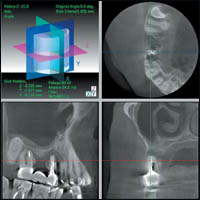

3 DX Accuitomo/FPD после исследования пациента сразу же воспроизводит на экране монитора ИСТИННОЕ трехмерное изображение в трех перпендикулярных друг другу плоскостях.(Рис 2)

Затем возможна реконструкция срезов в вертикальной и горизонтальной плоскости под любым углом к зоне зубочелюстной дуги.

Благодаря этому врач имеет возможность просмотреть изображение более детально (т.е. в трех плоскостях, а также послойно или с необходимым интервалом в режиме видеофильма). Трехмерное изображение 3 DX Accuitomo/FPD открывает новые возможности и перспективы планирования терапевтических, а также хирургических вмешательств в современной стоматологической практике и оториноларингологии (рис. 3).